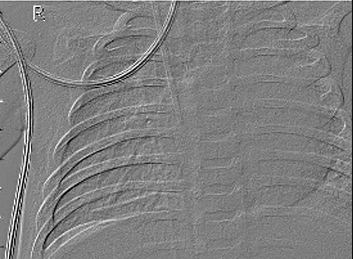

Table 6 Fused image output.

From: Multimodal medical image fusion combining saliency perception and generative adversarial network